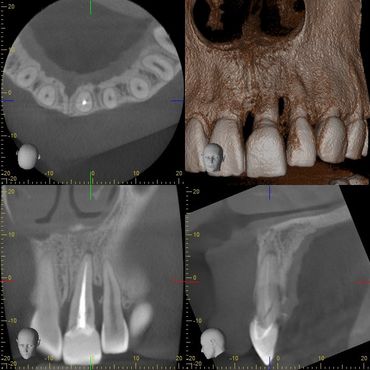

- Latest Cone Beam CT (3D) imaging for dental implant planning and endodontic treatment is available onsite